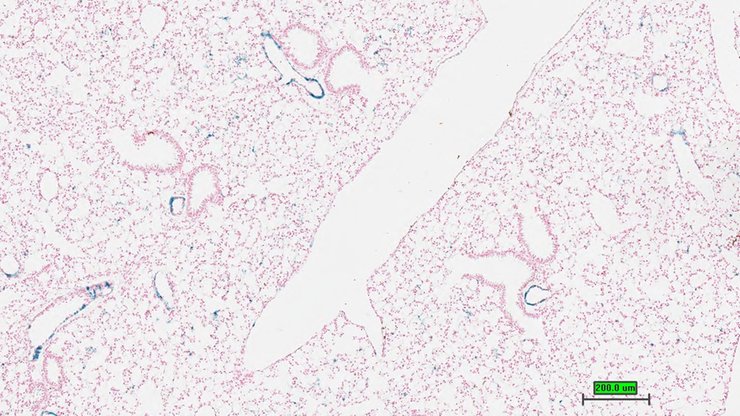

TS28: lung Present UC Davis_1861796

Specimen UC Davis_1861797: postnatal adult; Ccn5tm1.1(KOMP)Vlcg/Ccn5+ (more )

Structure Level Pattern Image Note

TS28: lung Present UC Davis_1861797

TS28: lung Present UC Davis_1861798

TS28: lung Present UC Davis_1861809